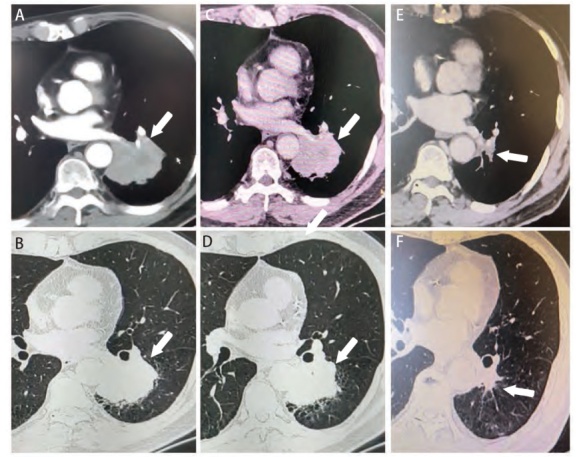

Mesenchymal-epithelial transition factor (MET) gene mutation is a large class of mutations commonly seen in non-small cell lung cancer (NSCLC). MET mutation includes subtypes such as MET exon 14 skipping mutation (METex14m) and MET amplification (METamp). For advanced NSCLC with METex14m, Savolitinib has a high sensitivity as a member of tyrosine kinase inhibitors (TKIs). METamp is a relatively rare genetic mutation type which can serve as a driver gene to mediate primary and later acquired drug resistance of epidermal growth factor receptor (EGFR)-TKIs. For advanced NSCLC with secondary METamp, EGFR-TKIs combined with MET-TKIs are usually used in clinical treatment, while the optimal treatment strategy for advanced NSCLC with primary METamp has not yet been determined. For locally advanced NSCLC patients with positive driver gene mutations such as EGFR, anaplastic lymphoma kinase (ALK) fusion and METex14m, there have been relevant cases reported that neoadjuvant targeted therapy could achieve a good prognosis, but there have been no cases of neoadjuvant targeted therapy for locally advanced NSCLC patients with METamp. This report describes a case of a locally advanced NSCLC patient with dual driver gene mutations (EGFR L858R combined with primary METamp), the tumor did not shrink after 1 month of Gefitinib monotherapy, but significantly subsided after 4 months of Savolitinib monotherapy. After radical surgery, the pathological results proved pathological complete response (pCR) of the tumor, and the patient had a good response to postoperative continual Savolitinib treatment, with no recurrence nor metastasis observed to date. This case reports the feasibility and effectiveness of neoadjuvant targeted therapy for locally advanced NSCLC with primary METamp, aiming to provide effective reference for perioperative treatment of locally advanced NSCLC with primary METamp.